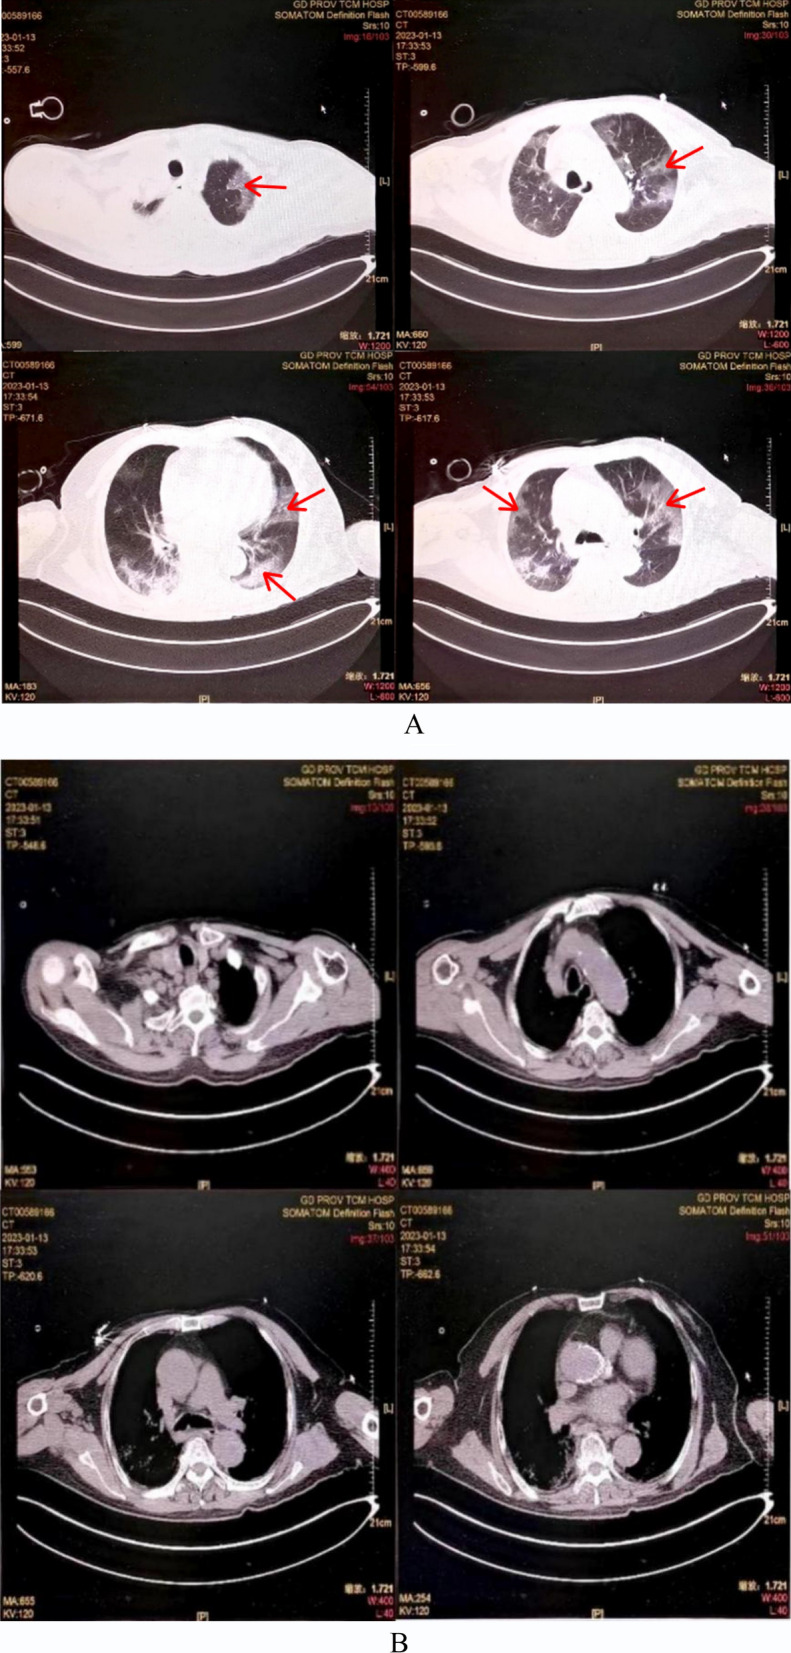

COVID-19-associated pulmonary aspergillosis (CAPA) significantly exacerbates the clinical outcomes of COVID-19 patients, contributing to heightened mortality. Aspergillus tracheobronchitis, a manifestation of invasive pulmonary aspergillosis, specifically involves the tracheobronchial tree. According to the 2020 European Confederation of Medical Mycology/International Society for Human and Animal Mycology (ECMM/ISHAM) consensus criteria, airway biopsy via bronchoscopy is the definitive method for CAPA diagnosis, underscoring its critical role in the management of COVID-19 patients. This case report describes an elderly male patient with COVID-19 who presented with extensive pseudomembranous involvement of the tracheobronchial tree, identified through bronchoscopy. The pseudomembrane, spanning from the glottis to the bronchi and characterized by its yellow-white translucency, was removed. Subsequent pathological examination and next-generation sequencing confirmed an Aspergillus infection. Despite the initiation of antifungal therapy, the patient's condition deteriorated, leading to his death.